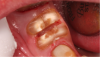

Mandibular molars can be sectioned bucco-lingually and each root removed individually. Maxillary molars are sectioned mesio-distally first, then the palatal root is removed bucco-lingually, and the buccal roots removed individually (Figure 3 through Figure 5). If clinicians are using an air-driven high-speed handpiece, they should not lay a flap as this may give the patient an air embolism.8 If a flap has been reflected, an electric handpiece must be used.

Fig 3. A nonrestorable molar.

Figure 3

Fig 4. Careful sectioning has been performed.

Figure 4

Fig 5. Atraumatic tooth removal.

Figure 5